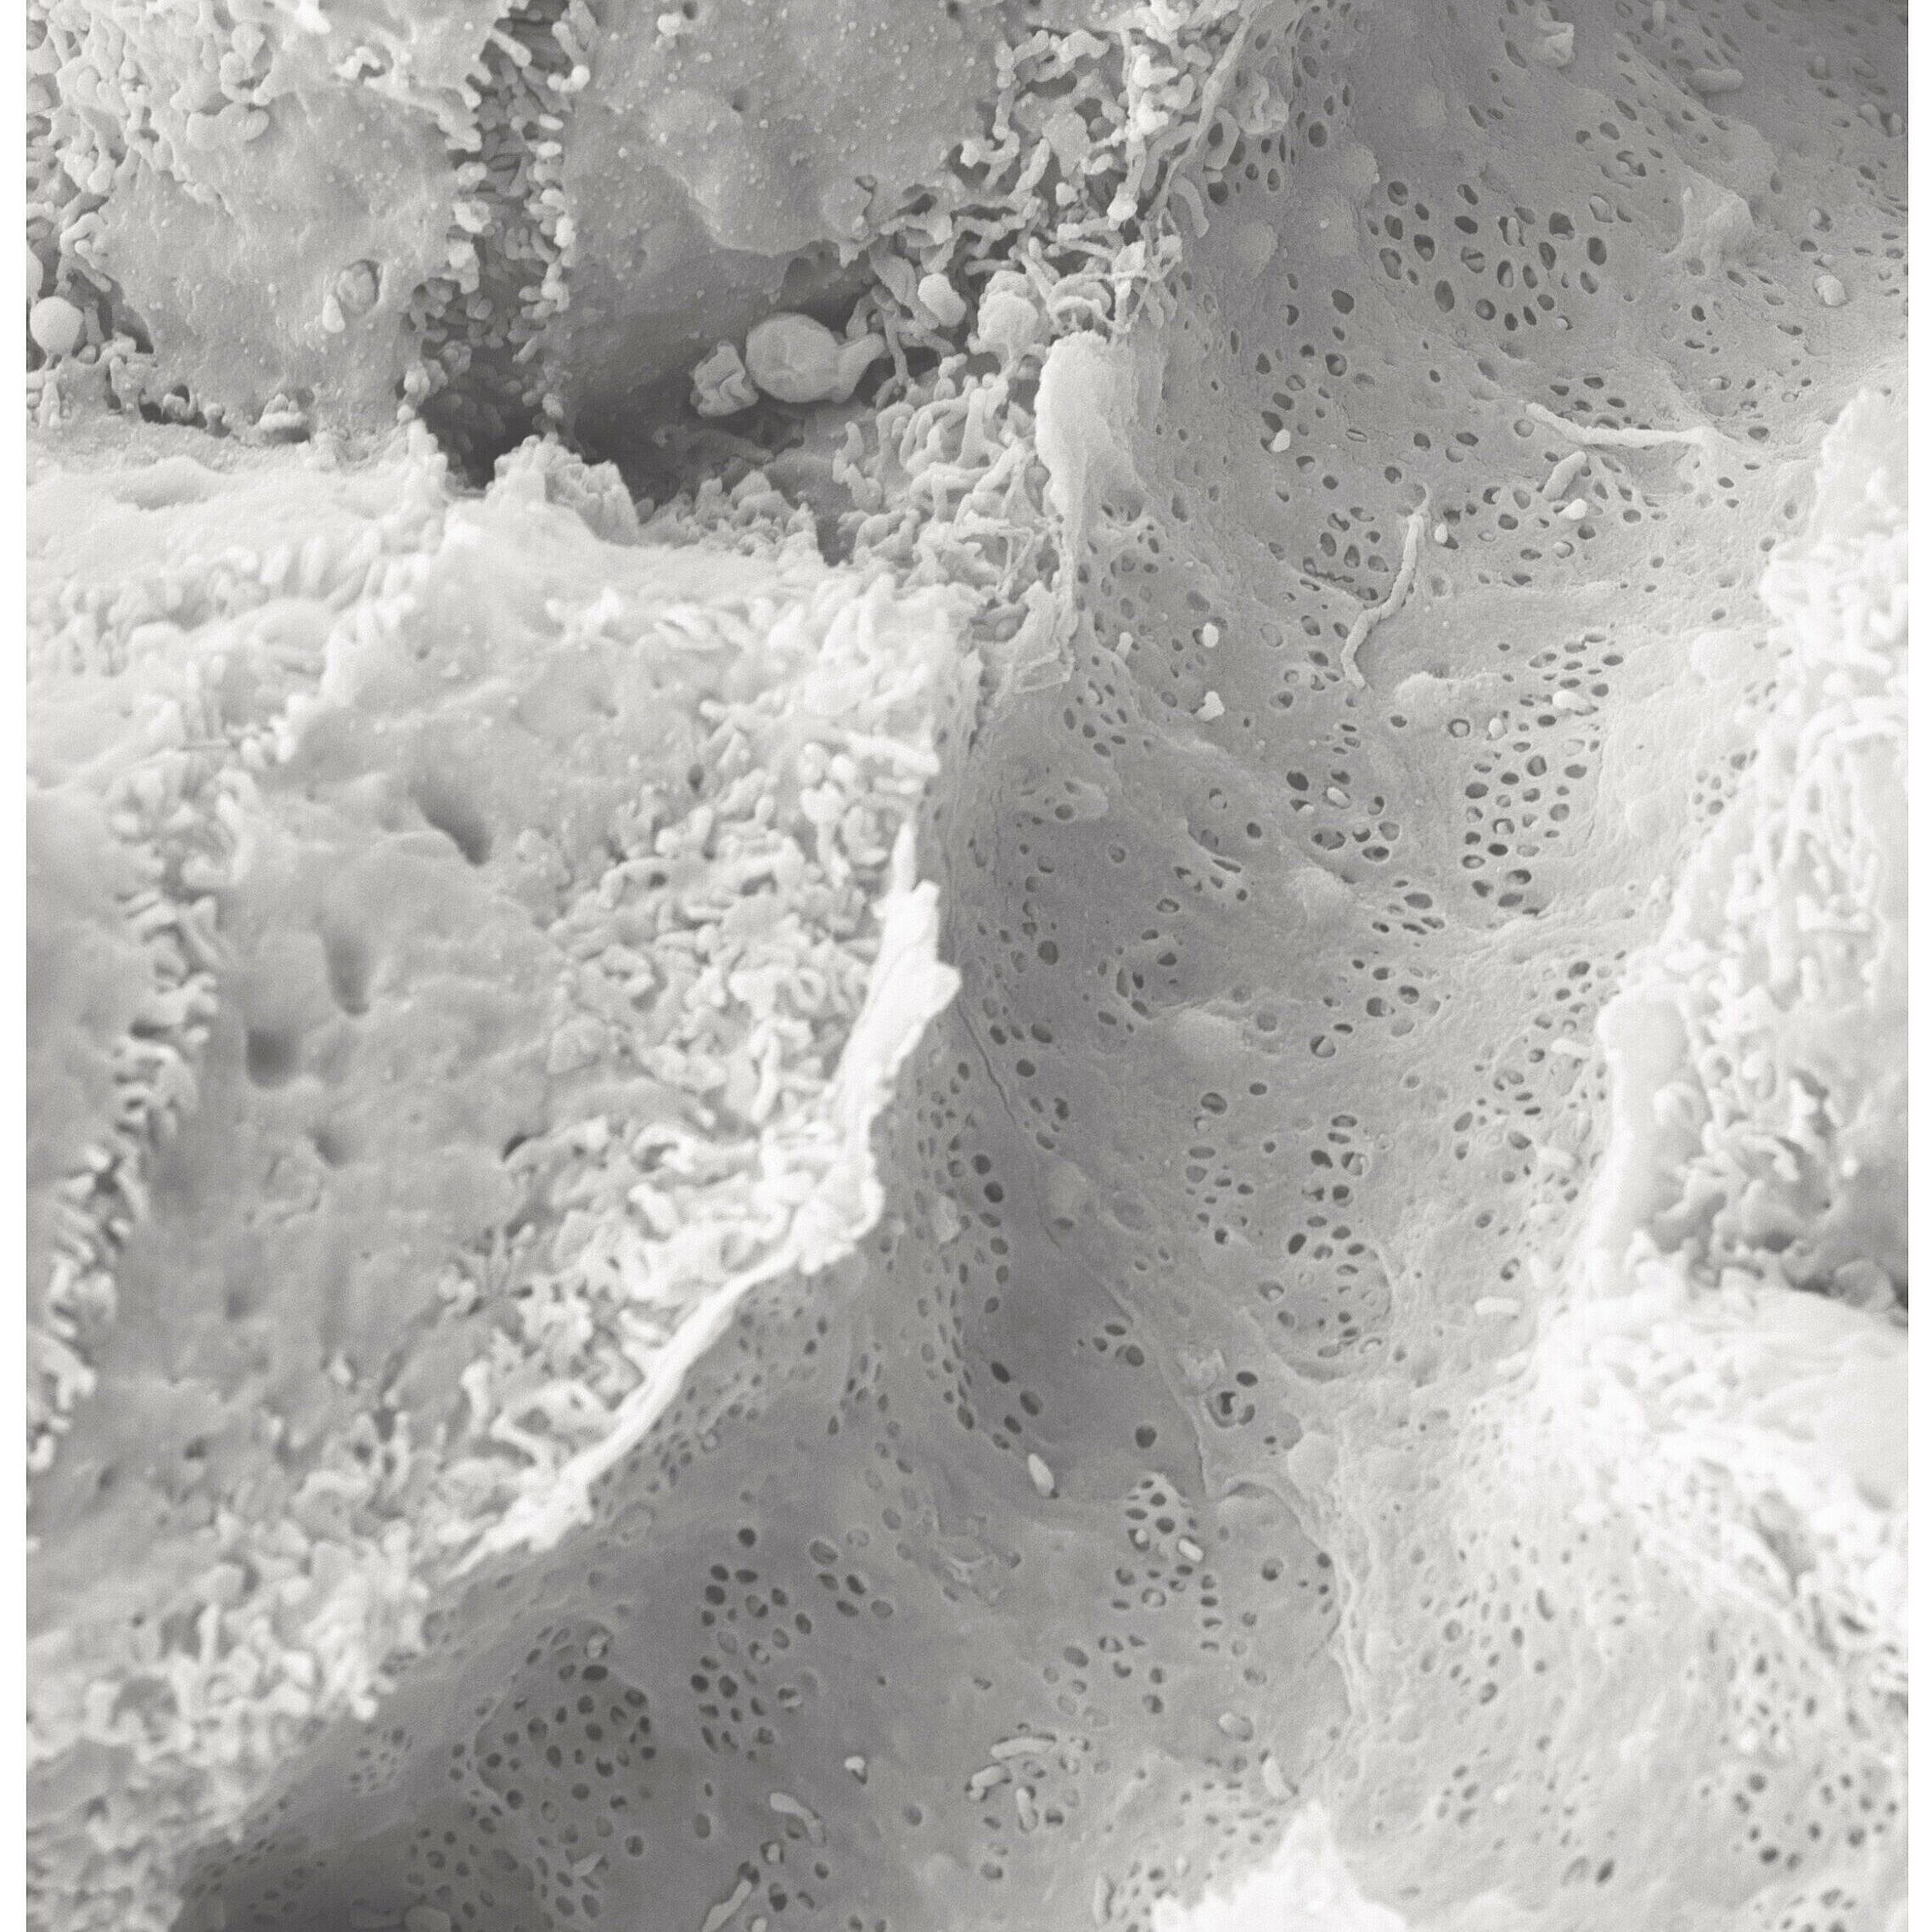

Scanning electron micrograph of a small blood vessel in the liver, which contains many windows (small, dark grey dots).

The leading role is played by windows (Latin: fenestrae) in the endothelial cells of blood vessel, through which substances are exchanged between liver cells and blood. The liver uses these tiny windows to release excess fat particles into the adipose tissue via the bloodstream. The researchers discovered that these windows are closed by a mechanism in which the signalling molecule SEMA3A (semaphorin-3A) plays the central part. This molecule is produced in blood vessels when they are overly exposed to the saturated fatty acid “palmitic acid“.

Sydney Balkenhol from the Institute of Metabolic Physiology at HHU and the DDZ, first author of the study now published in Nature Cardiovascular Research, points to a discovery made by the team using scanning electron microscopy: The “windows” in the smallest blood vessels of the liver were also closed in mice with fatty liver and type 2 diabetes mellitus.